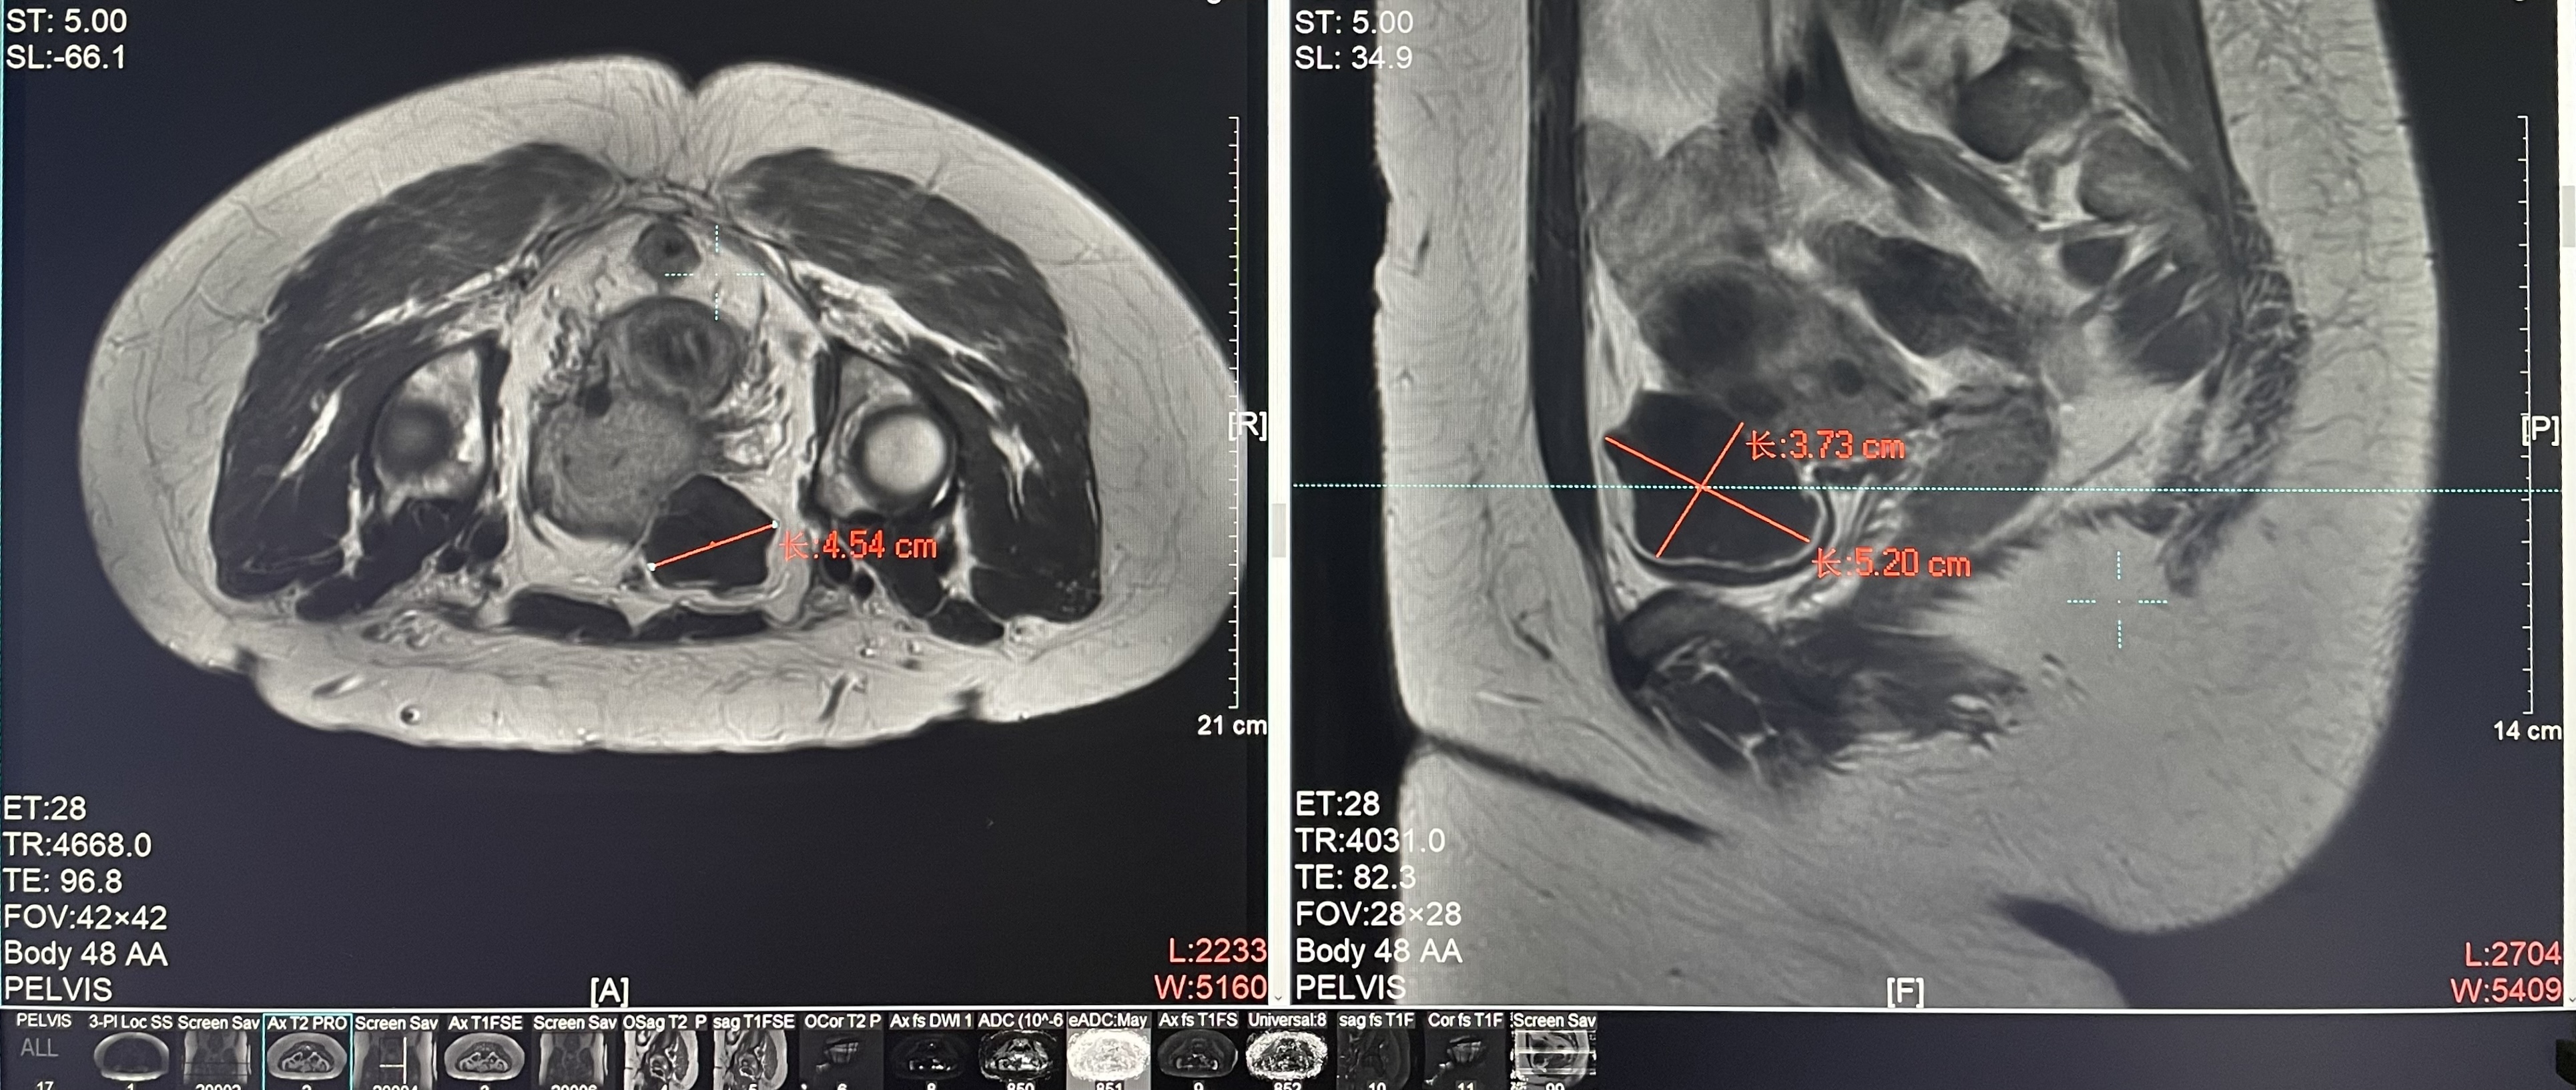

患者信息:女,38

診斷:子宮肌瘤

腫瘤尺寸:約為45*52*38mm

ROT深度:腫瘤的ROT中心距離皮膚62mm

術后評估:術后造影增強圖像顯示消融區(qū)域(右側)與腫瘤區(qū)域(左側)重合度較好,非灌注區(qū)域連續(xù)且一致。

結論:對該腫瘤具有非常好的消融效果,治療過程中,溫度上升曲線符合預期,每個被治療的靶點240CEM區(qū)域體積較大、外形飽滿、連續(xù)。病灶消融良好,NPV體積比約88.7%。